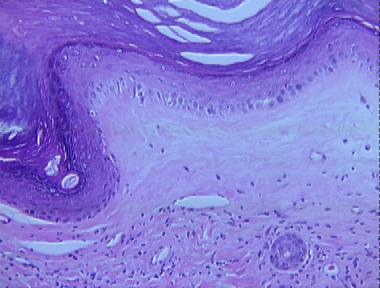

lichen sclerosis et atrophicus, old

Histologic Features